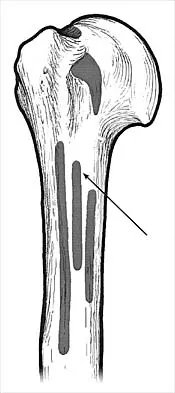

What muscle attaches to the site shown by the arrow in Figure 2?

Explanation